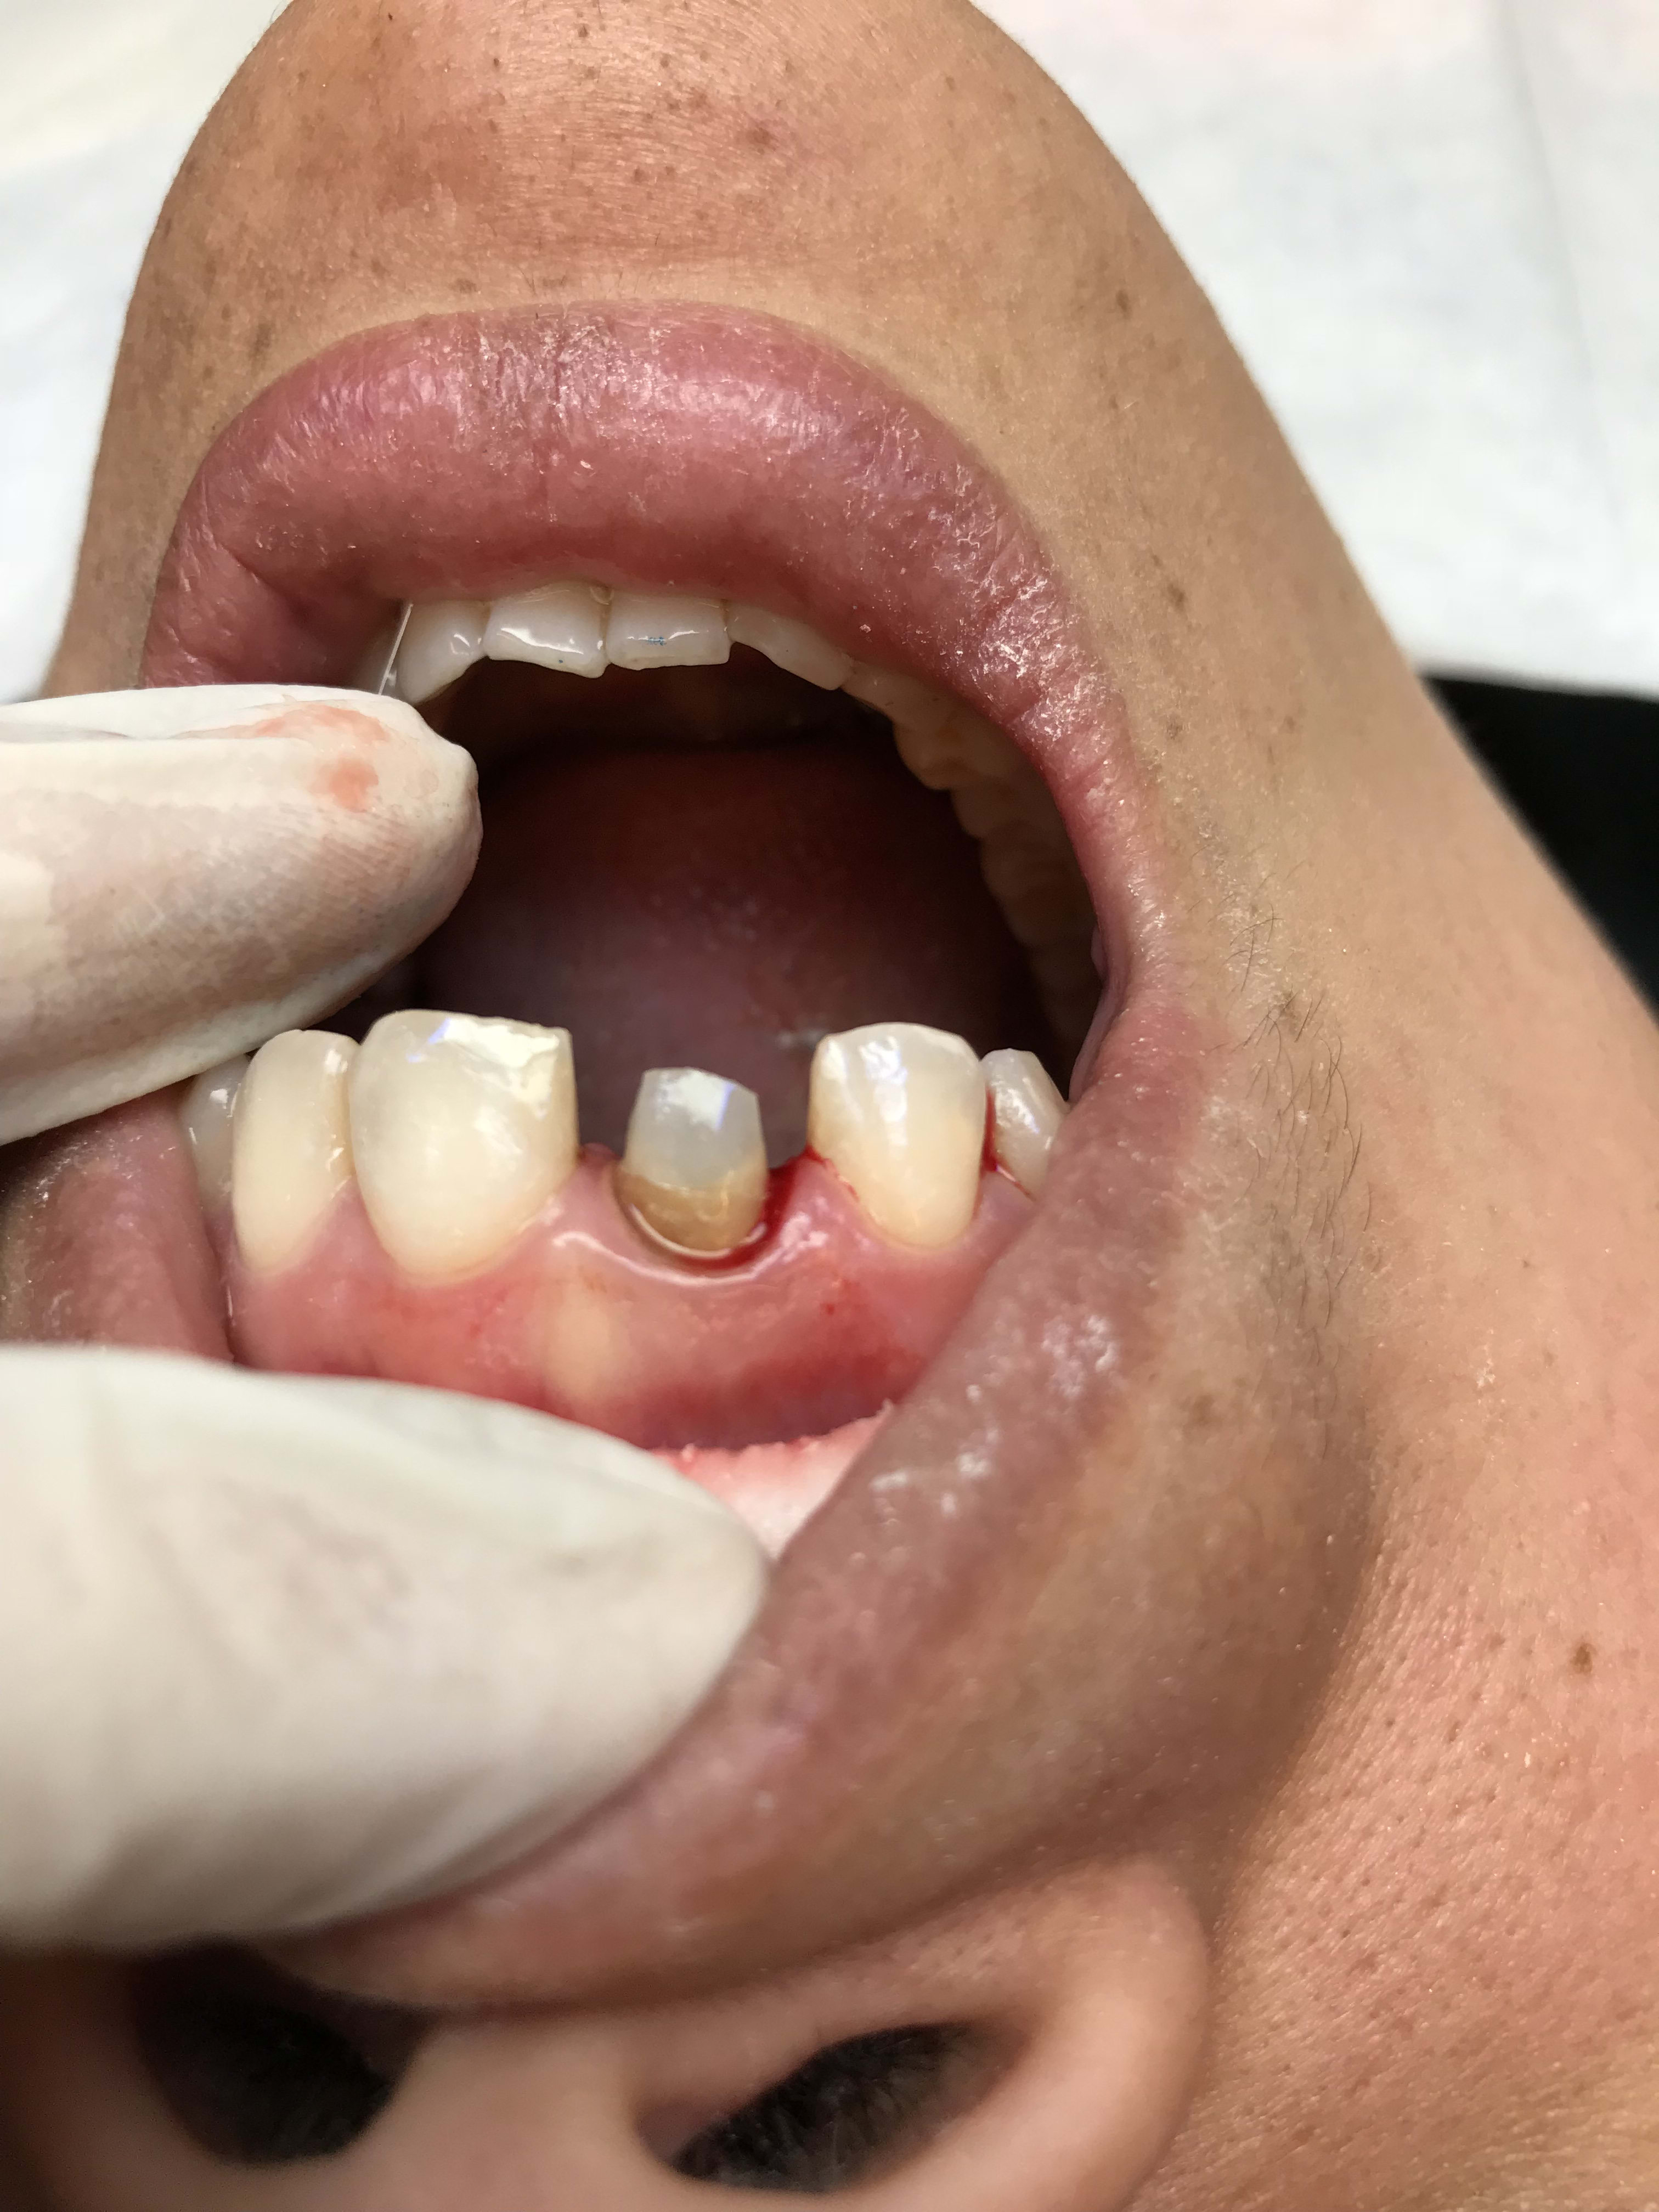

protection d'une plaie et de la suture.